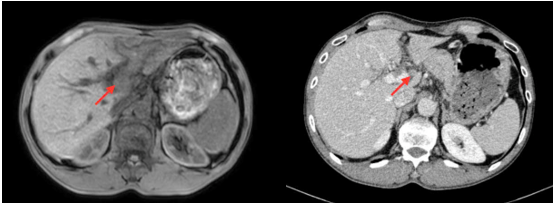

Hình 1. Hình ảnh chụp cộng hưởng từ ổ bụng

Hình ảnh gan biến đổi hình thái, bờ không đều. Nhu mô gan trái có đám tổn thương sau tiêm ngấm thuốc không đều, tổn thương xâm lấn theo tĩnh mạch cửa nhánh trái vào thân chung gây huyết khối nhánh trái và thân chung tĩnh mạch cửa (mũi tên vàng) tạo đám tổn thương kích thước khoảng 55x77mm (mũi tên đỏ)

Sau điều trị 2 chu kỳ, bệnh nhân dung nạp thuốc tốt, các triệu chứng trước điều trị giảm, tác dụng phụ chủ yếu thường gặp là buồn nôn sau truyền. Trên phim cắt lớp vi tính sau 2 tháng điều trị: Hình ảnh gan kích thước bình thường, bờ đều, nhu mô đồng nhất trước và sau tiêm thuốc cản quang. Không thấy khối khu trú. Rốn gan có vài hạch, lớn nhất kích thước 15x11mm. Tĩnh mạch cửa không giãn, đường kính bình thường, huyết khối hoàn toàn nhánh trái tĩnh mạch cửa lan vào 1 phần nhỏ thân chung, sau tiêm ngấm thuốc nhẹ.

Hình 2. Hình ảnh so sánh giữa cộng hưởng từ tháng 10 và cắt lớp vi tính tháng 12